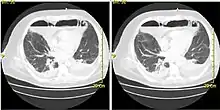

Acute mediastinitis can be confirmed by contrast x-rays since most cases of acute mediastinitis are due to esophageal perforation. Other studies that can be used include endoscopic visualization, Chest CT scan with oral and intravenous contrast.

With regards to CT Imaging, the extent of involvement of the mediastinum can be evaluated. Therefore, acute mediastinitis can be classified into three categories:[6]

- diffuse mediastinitis

- isolated mediastinal abscess

- mediastinitis or mediastinal abscess complicated by empyema or subphrenic abscess.